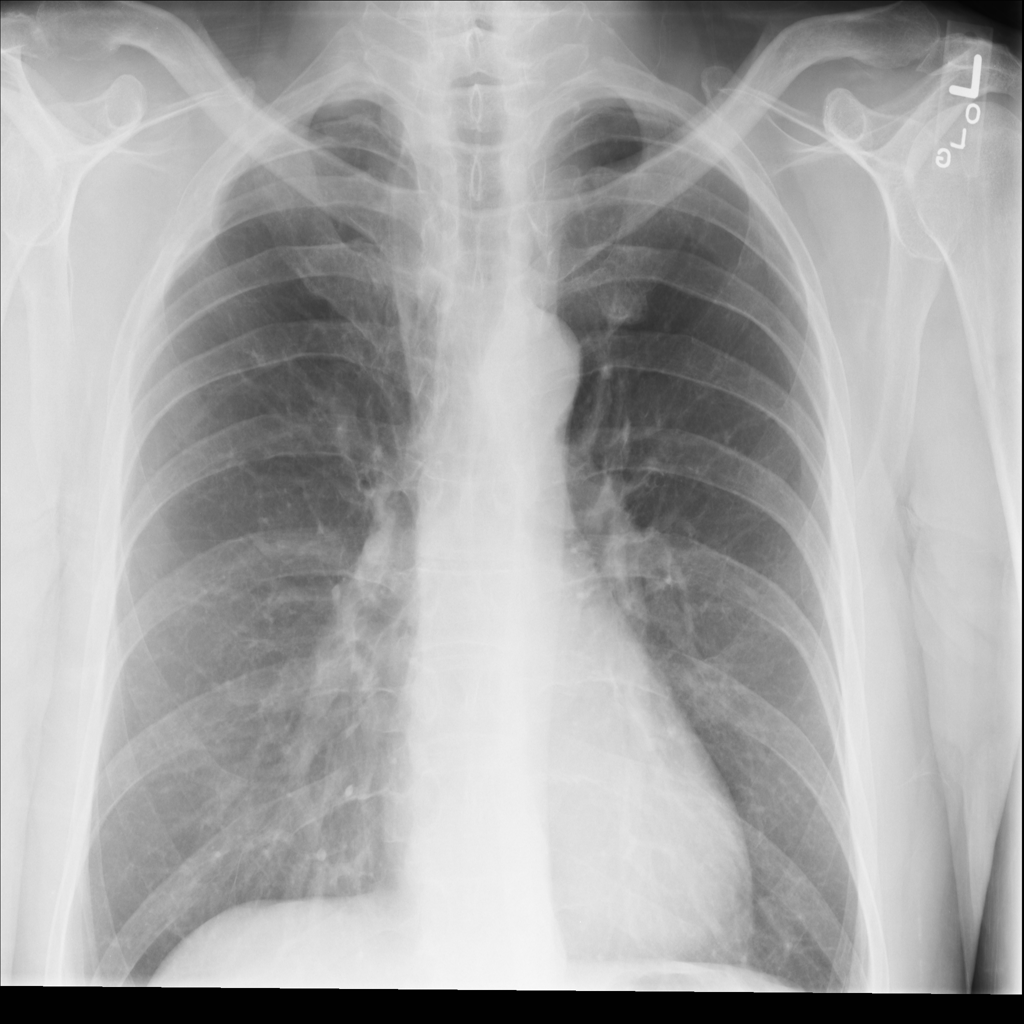

Mass

A mass is a larger focal opacity or lesion seen on the image. It is a descriptive finding that can have several causes and usually needs more imaging or clinical context to characterize.

PAT-2F7C · IMG-000Mass

PAT-2F7C · IMG-000

PA